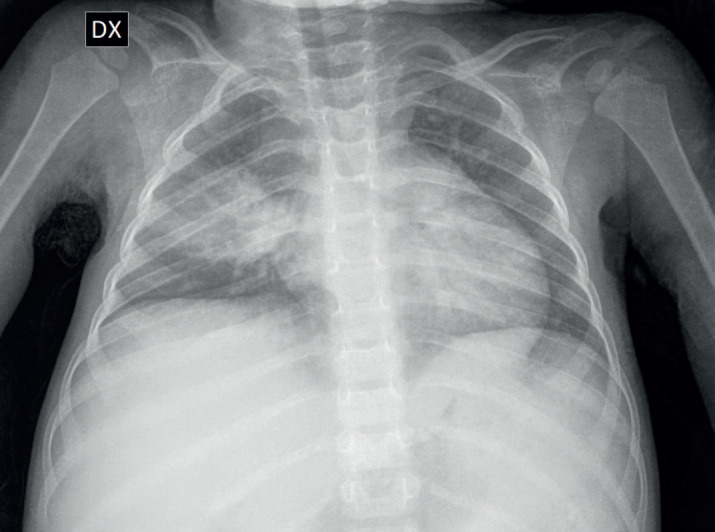

Case presentation: In children, TB often presents with a wide range of non-specific clinical and radiological manifestations, making diagnosis challenging, particularly in regions with low prevalence. We report the case of a two-year-old female with a history of constipation, weight loss, marked abdominal distension with hepatosplenomegaly, who was later diagnosed with miliary tuberculosis.

Conclusion: This case highlights an unusual presentation of miliary TB in a very young child, a demographic in which it is infrequently observed. Miliary TB remains a severe and potentially fatal condition, particularly when diagnosis and treatment are delayed. The diagnosis is usually made based on the clinical presentation, supported by a classic miliary pattern on chest X-ray.